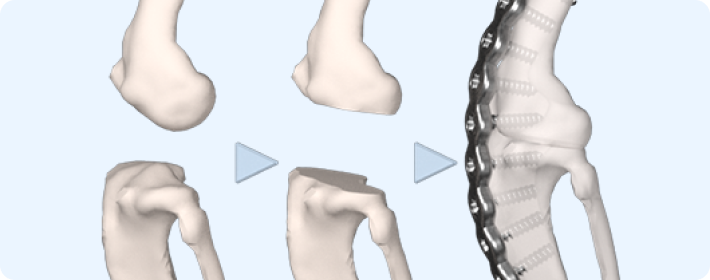

교정절골술

무릎이나 엉덩이 관절의 이상 정렬을 교정하기 위해 뼈를 절개하고 재정렬하는 수술입니다. 관절의 부담을 줄여 통증을 완화하고 기능을 개선하는 목적이 있습니다.